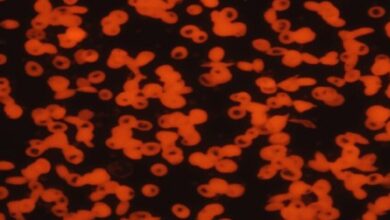

أوضح الباحثون أن كلا المرضين يشتركان في آليات التهابية مشتركة، مثل اضطرابات المناعة واختلال التوازن الميكروبي، مما يزيد من سوء حالة الأسنان والكلى معا، وأشاروا إلى أن مرضى الكلى المزمن الذين يعانون أيضا من أمراض اللثة هم أكثر عرضة للإصابة بأمراض مزمنة أخرى، مثل السكري وارتفاع ضغط الدم، مما يعقّد علاجهم ويزيد من احتمالات دخولهم المستشفى.

ويؤكد الكثير من خبراء الصحة على أن تنظيف الأسنان بانتظام يقلل من معدلات البكتيريا الضارة التي تسبب الالتهابات في الجسم، ما ينعكس إيجابا على صحة الجسم./انتهى